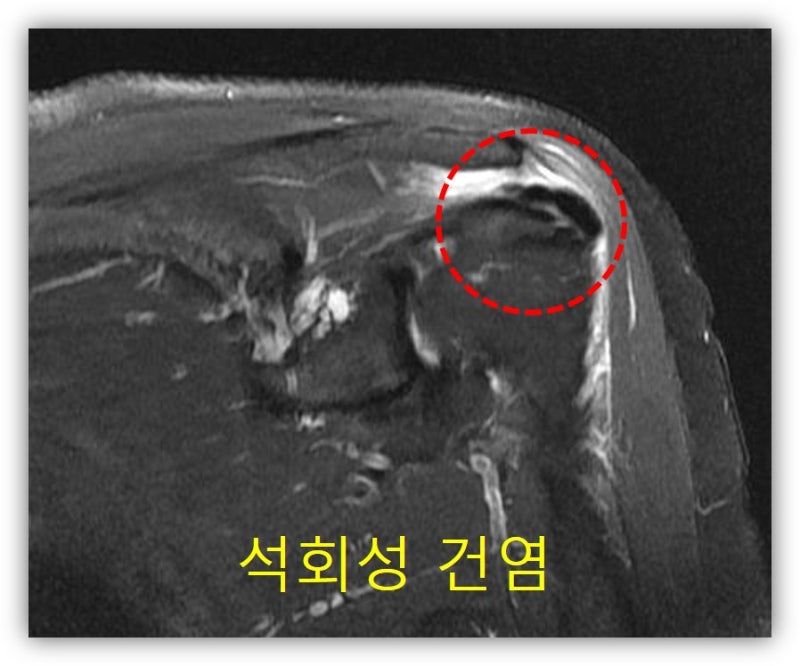

석회가 아주 큰 경우, 그리고 오래된 경우 회전근개의 손상이 있을 가능성이 있어 MRI 검사도 시행하였습니다.

석회성 건염을 오래 앓다 보니 관절낭의 구축까지 있어 가동범위 제한도 심하게 있었습니다. 환자에게 뉴핌스 치료를 시행하였습니다. 관절낭의 구축을 풀어주고 석회분쇄흡입술을 시행하였습니다.